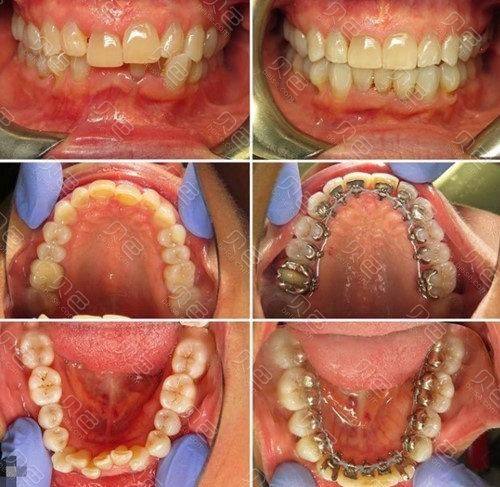

1. 牙齿矫正:毛治军 医生在牙齿矫正方面有着丰富的经验。他会根据患者的牙齿情况和面部特征,制定出更适合的矫正方案。比如对于牙齿排列不齐、咬合不正等问题,他能运用精良的矫正技术,帮助患者拥有整齐美观的牙齿。在矫正过程中,他会密切关注患者的牙齿移动情况,及时调整矫正方案,确保矫正成效达到至佳。

1. 患者李先生:我一直有牙齿不齐的问题,特别影响美观。在朋友的推荐下,我找到了毛治军 医生。毛医生非常耐心地给我分析了牙齿情况,还为我制定了详细的矫正方案。在矫正过程中,他会经常关心我的牙齿状况,及时调整矫正力度。现在我的牙齿已经变得整齐多了,笑容也更加自信了。真的非常感谢毛医生,他的技术和服务都让我非常满意。